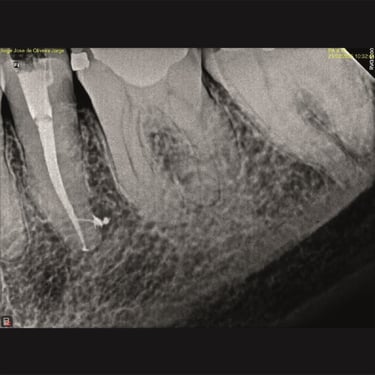

Remoção de pinos intrarradiculares:

Remoção de pinos metálicos que impedem novos tratamentos ou reabilitação protética.

Retiradas de instrumentos fraturados:

Extração de fragmentos de limas ou outros instrumentos quebrados durante procedimentos anteriores.

CASOS CLÍNICOS ENDO

Abaixo você encontra fotos de alguns dos tratamentos realizados.